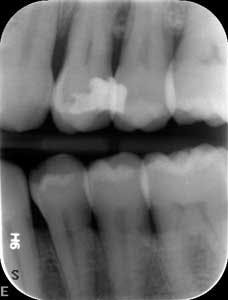

Dental examination revealed gingival swelling and bleeding on probing. Periodontal probing showed moderate-to-deep pocket depths in all posterior teeth (figures 1–3). Generalized bone loss was observed on radiographs (figures 4–6). Tooth vitality and percussion tests were negative. Teeth 2, 3, 31, 14, and 15 had Class III mobility. The patient was diagnosed with Type IV chronic adult periodontitis. Treatment options were discussed, and, after explanation, the patient agreed to the LANAP procedure.

At nine months, the patient’s tissues appeared pink with no inflammation. Radiographs revealed new bone growth, especially around teeth Nos. 3, 15, and 31 (figures 10–12). The patient reported his HbA1c level stable at 8.2.

Patient presentation before LANAP treatment (figures 1–6)

Radiographs nine months after LANAP treatment (figures 10–12)